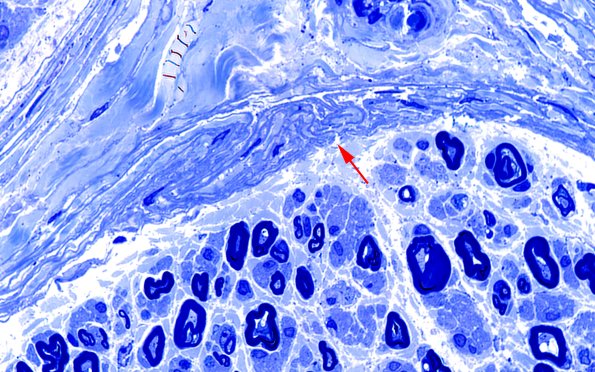

Washington University Experience | PERIPHERAL NEUROPATHY | 9B PERINEURITIS & PERINEURIAL PATHOLOGY | 12A2 Perineurium, papillary basal lamina (Case 12) Plastic 100X 3 copy

Plastic sections show modest loss of small and large myelinated axons. The perineurium appears hyperplastic and papillary (arrow)